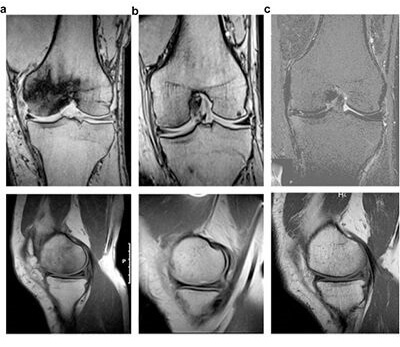

Ibrahim Bozkurt, Nadir Yalcin, Enes Uluyardimci, Esra Artvinli Akgul

Volume 32, Issue 6; https://doi.org/10.1177/11207000211003285